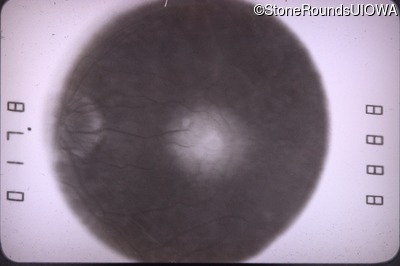

Infrared Fundus Photograph - Right - 20/60 -1

Exemplar